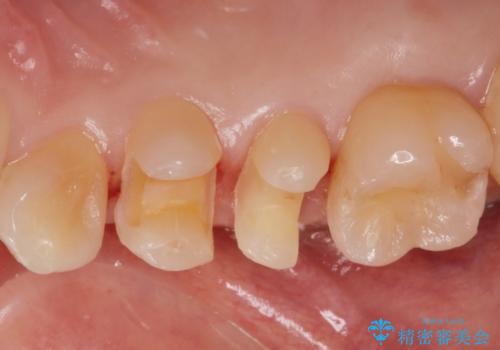

- 歯と歯の間に古い樹脂の治療がされていて虫歯の再発のリスクが高まるためにe-maxインレー(セラミック)治療を行いました。